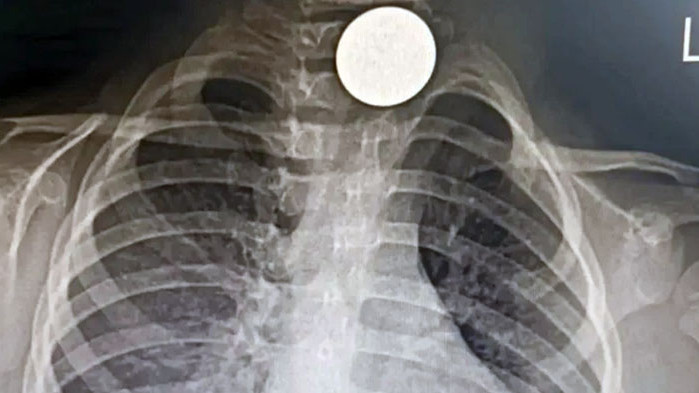

Преди десетина дни дребната ненадейно стартира да подвига висока температура, а фотография на белия дроб демонстрира монета на входа на хранопровода – в края на гърлото. Монетата е извадена в УМБАЛ Бургас от доцент доктор Даниел Петков и доктор Ивайло Илиев.